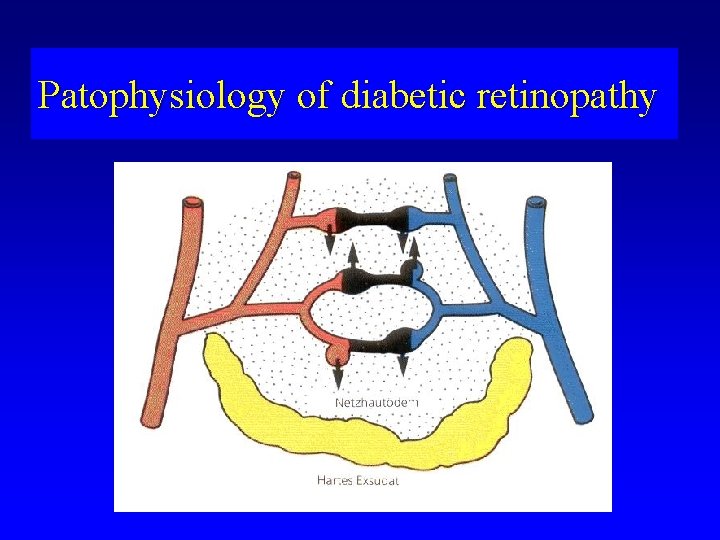

Patophysiology of diabetic retinopathy

Diabetic makulopathy (M) • Macular area is a predilection site for edema formation Microangiopathy leads to ischemia, fluid accumulation, formation of microcysts and cysts Hard exudates (lipid accumulation) occur on the boundary of ischemic and normal retina